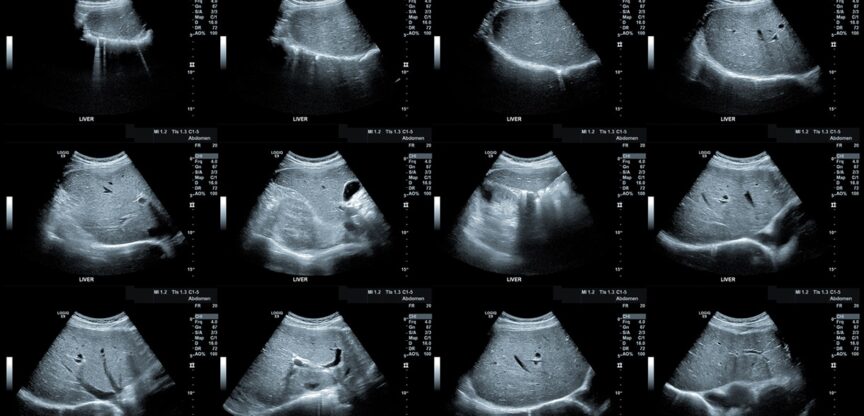

Weil die Fettleber von den Betroffenen selbst kaum bemerkt wird, entdeckt man sie oft zufällig: „Sehr oft erfolgt die Diagnose bei einer Kontrolle der Blutwerte, z. B. vor einer geplanten Operation oder im Rahmen einer Vorsorgeuntersuchung“, sagt Hofer. „Wenn das Blutbild zeigt, dass die Leberwerte und bestimmte Blutfettwerte erhöht sind, deutet das auf eine Fettleber hin.“ Ob man aber wirklich eine Fettleber hat, bei der die Leberzellen durch die Einlagerung von Fett sozusagen lahmgelegt sind und ihre Funktion nicht mehr erfüllen, können nur weiterführende Untersuchungen zeigen. Dazu zählt zunächst eine Untersuchung, bei der festgestellt wird, ob die Leber so vergrößert ist, wie es für eine Fettleber typisch ist. Anschließend wird ein Ultraschallbild von der Leber gemacht, auf dem man sieht, ob das Lebergewebe entsprechend verändert ist. Um andere Lebererkrankungen auszuschließen, erfolgt noch eine Leberbiopsie, bei der unter örtlicher Betäubung und nach einer Punktion Gewebe aus der Leber entnommen wird.